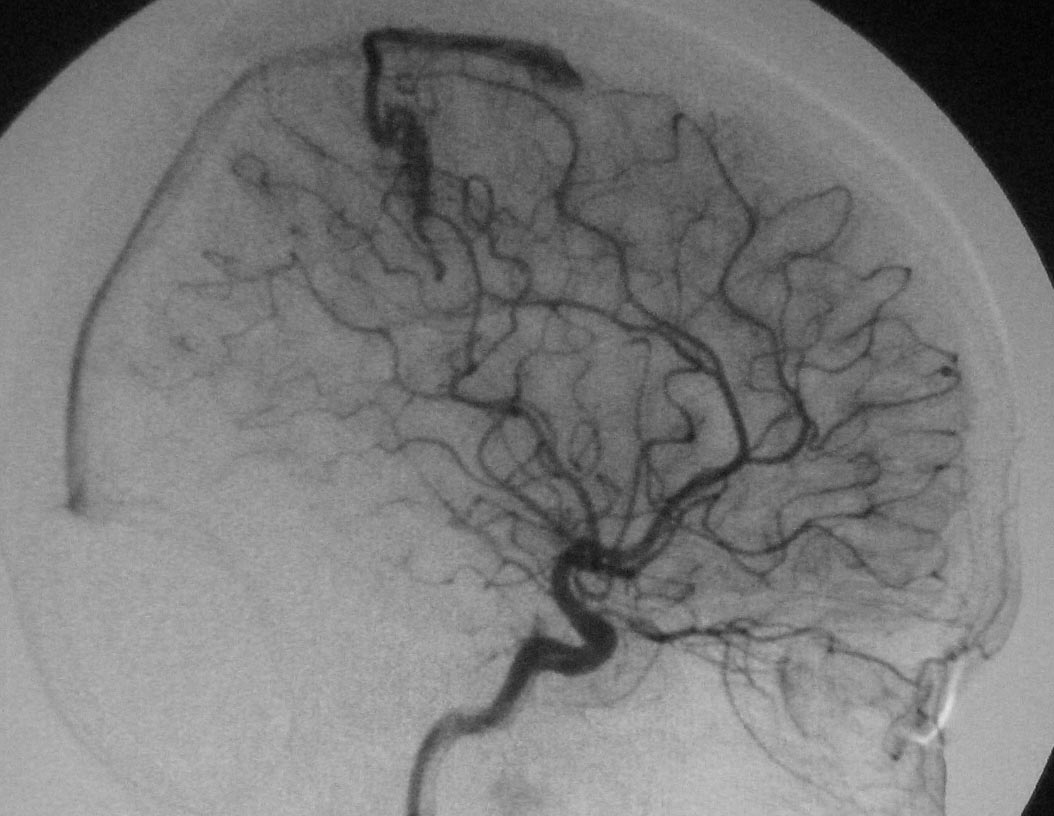

标题: DSA0118:脑血管造影

典型的avm

有供血动脉、畸形血管团、引流静脉,支持典型avm。

大脑中动脉的皮质支通过引流静脉汇入上失状窦